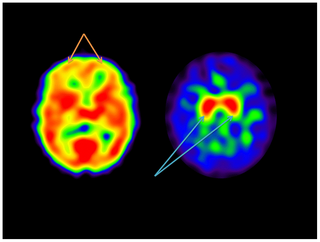

Research Article

J Otol Rhinol 2013, 2:1

10.4172/2324-8785.1000111

Research Article

J Otol Rhinol 2013, 2:1

10.4172/2324-8785.1000112